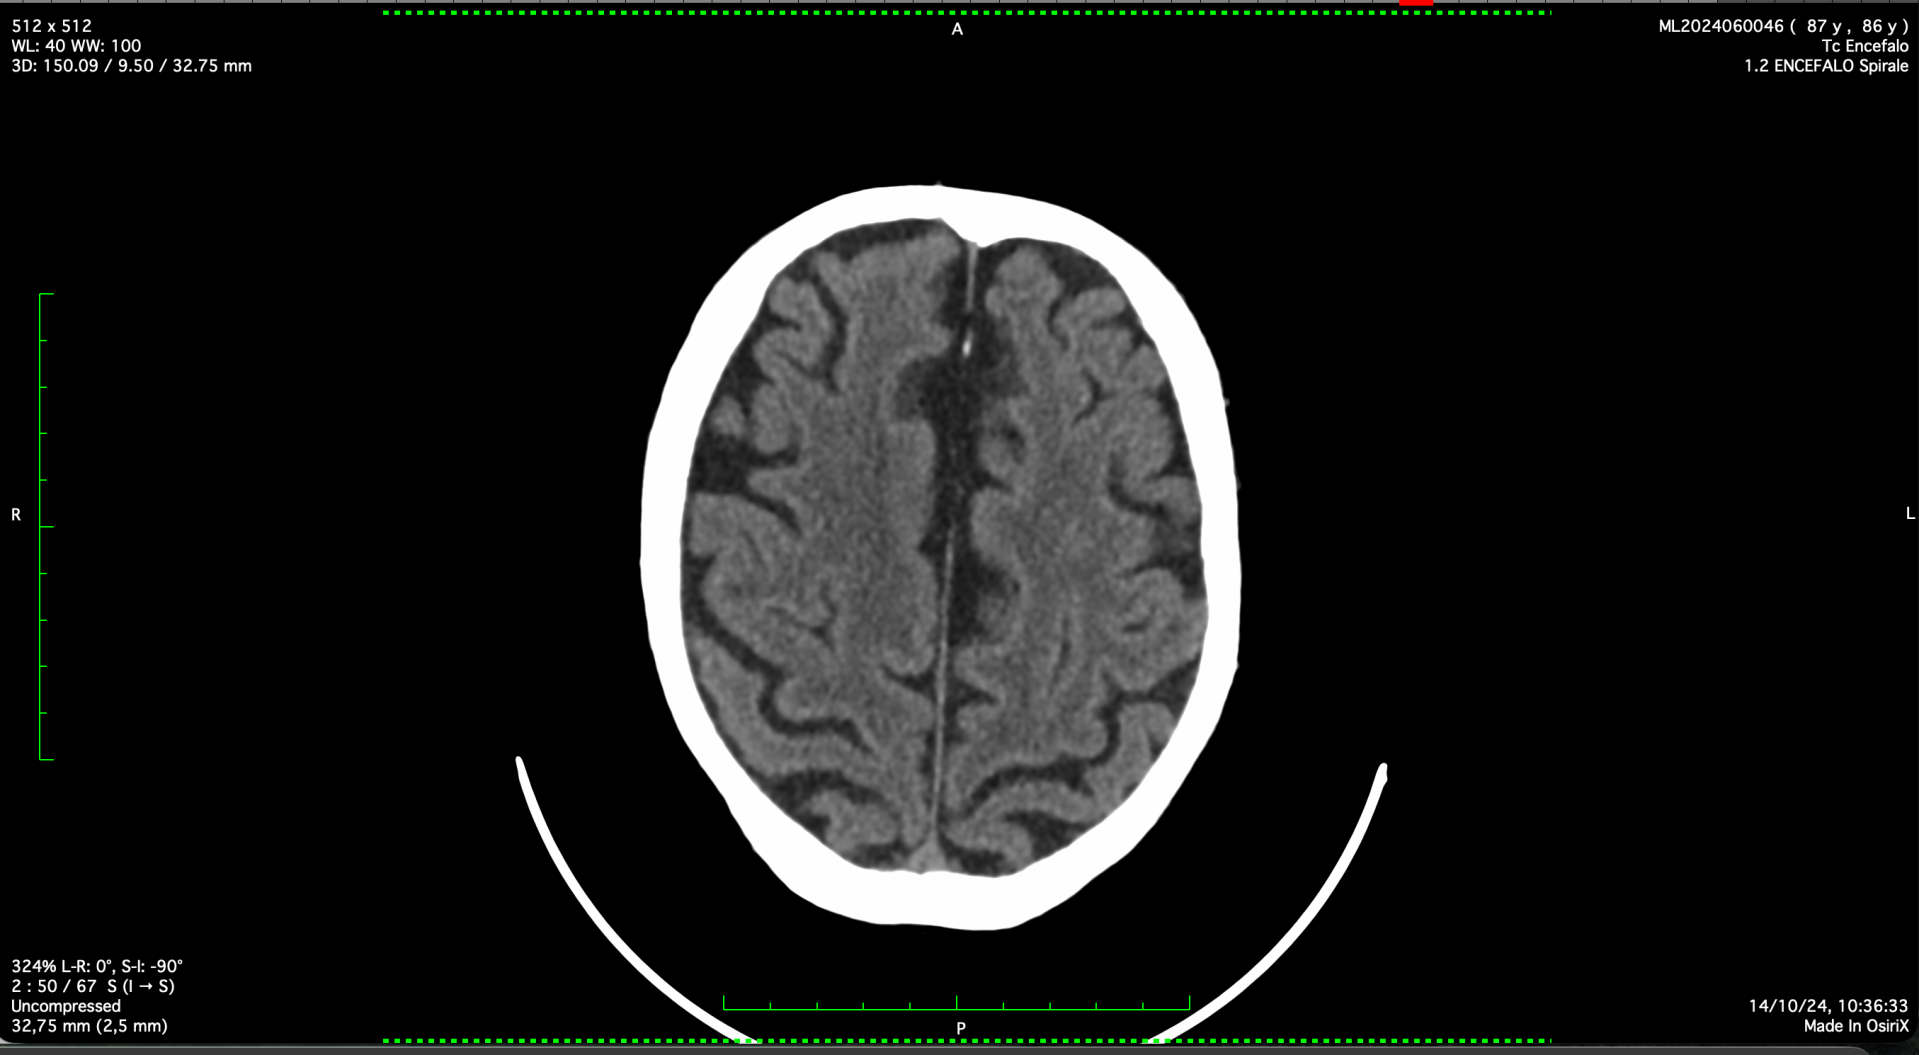

No farther than 19 months later, as of October 14th 2024, by directly tackling the responsible pathogen, the brain imaging (TC this time) appeared sufficiently normalised,  what's more corresponded by a perfect brain performance, completely regained from the previous assessment, when central neurological capability was affected (wake/sleep inversion, modified temper, paraparesis, and paraplegia),  and completely granting a normal, efficient, and functional relationship's life.